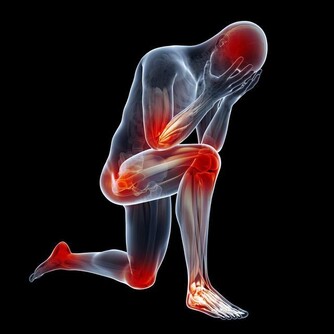

但剩下2/3症狀可能會愈來愈糟(約3成患者會惡化成乾癬性關節炎),

且必須一直持續治療,嚴重的話甚至會無法行走。

醫師建議乾癬患者務必注意關節症狀,像是早上起床,

關節紅腫脹痛特別明顯的人最好趕緊就醫,以免惡化至關節變形,造成不可挽回的悲劇。